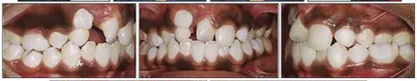

咬合關(guān)系:右側(cè)磨牙有II類關(guān)系傾向,尖牙關(guān)系II類;左側(cè)磨牙關(guān)系完全I(xiàn)I類,尖牙關(guān)系I類。上頜雙側(cè)反合,中線稍有偏離。覆合、覆蓋減少。上頜中切牙向腭裂側(cè)旋轉(zhuǎn),上頜右側(cè)尖牙頰側(cè)異位萌出,雙側(cè)乳尖牙仍存在?;颊呱项M弓嚴(yán)重?fù)頂D(擁擠度約10mm),下頜弓輕度擁擠4mm(擁擠度約4mm)(圖1 ;圖2)。牙周檢查良好。